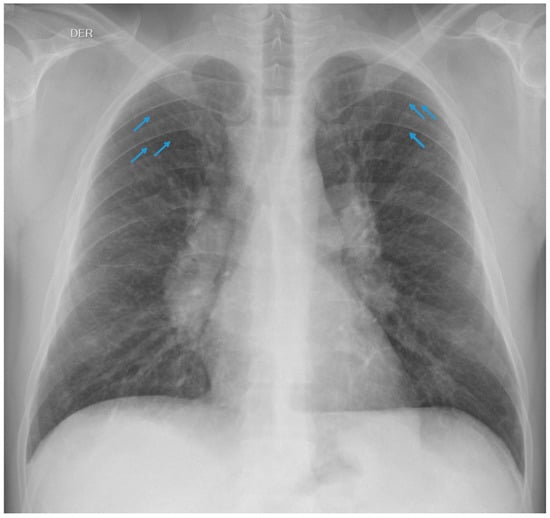

3.1.1. Case 1

3.1.2. Case 2